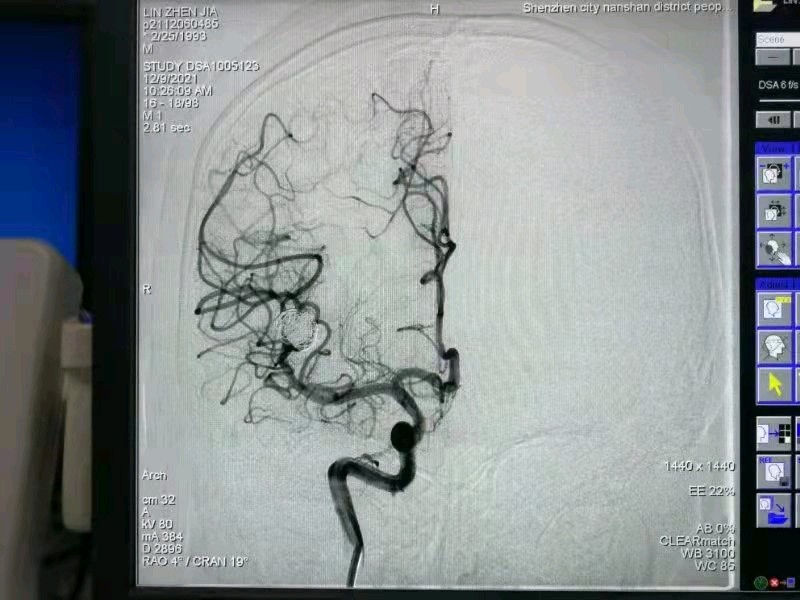

这个年轻患者在有效抗感染治疗的同时,优先处理 介入弹簧圈栓塞右侧脑动脉瘤,避免体外循环手术脑出血死亡风险。限期处理感染的二尖瓣,替换27 #St. Jude. 机械瓣,手术效果良好,术后规律抗感染治疗6周,康复出院!